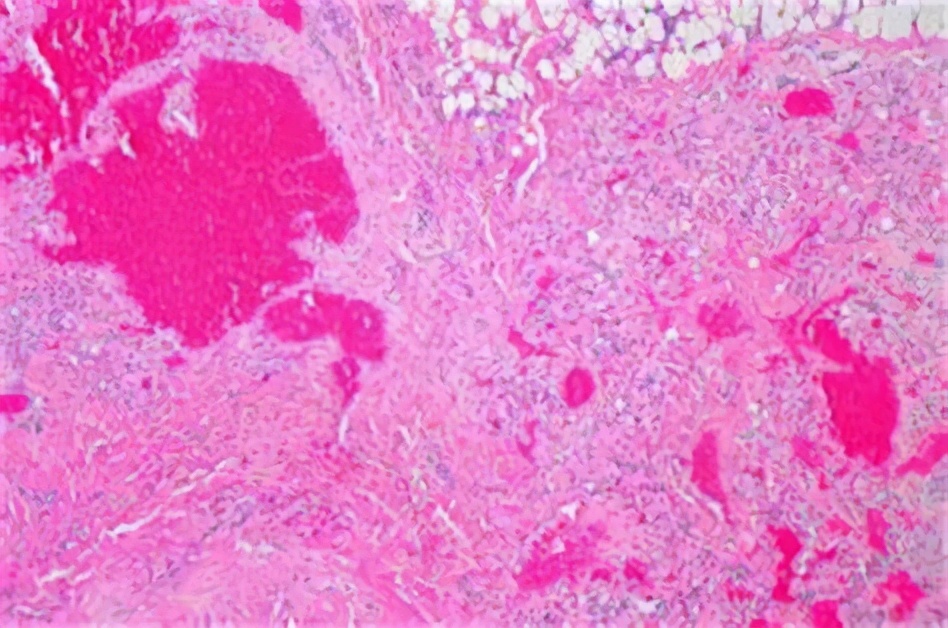

为了看得更细,切片可以放在显微镜下观察,能够看到更细微的结构,主要是有大小不等的海绵状血管腔,腔的内表面的内皮细胞内充满着血液,可能会发现血栓、结节和钙化。